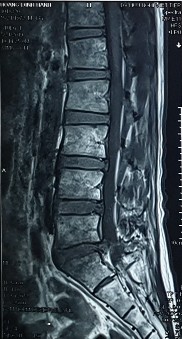

1. Hình ảnh khảo sát dẫn truyền thần kinh, điện cơ đồ và MRI (thực hiện trên mẫu nghiên cứu: bệnh nhân Nguyễn Văn H., mã số bệnh nhân 731711).

Bệnh nhân H., khi khám lâm sàng có biểu hiện tổn thương rễ thần kinh L3, L4, L5. Kết quả xét nghiệm điện cơ thấy: dẫn truyền thần kinh bình thường, nhưng kết quả khi điện cơ kim có biểu hiện tổn thương rễ thần kinh L4 . Kết quả chụp cộng hưởng từ là tổn thương thoát vị L4 – L5 . Như vậy, trên bệnh nhân này vị trí tổn thương thực tế khi kết hợp phối hợp giữa khám lâm sàng, chẩn đoán hình ảnh và chẩn đoán chức năng là vị trí rễ thần kinh L4.

Hình ảnh thoát vị đĩa đệm trên phim chụp MRI.